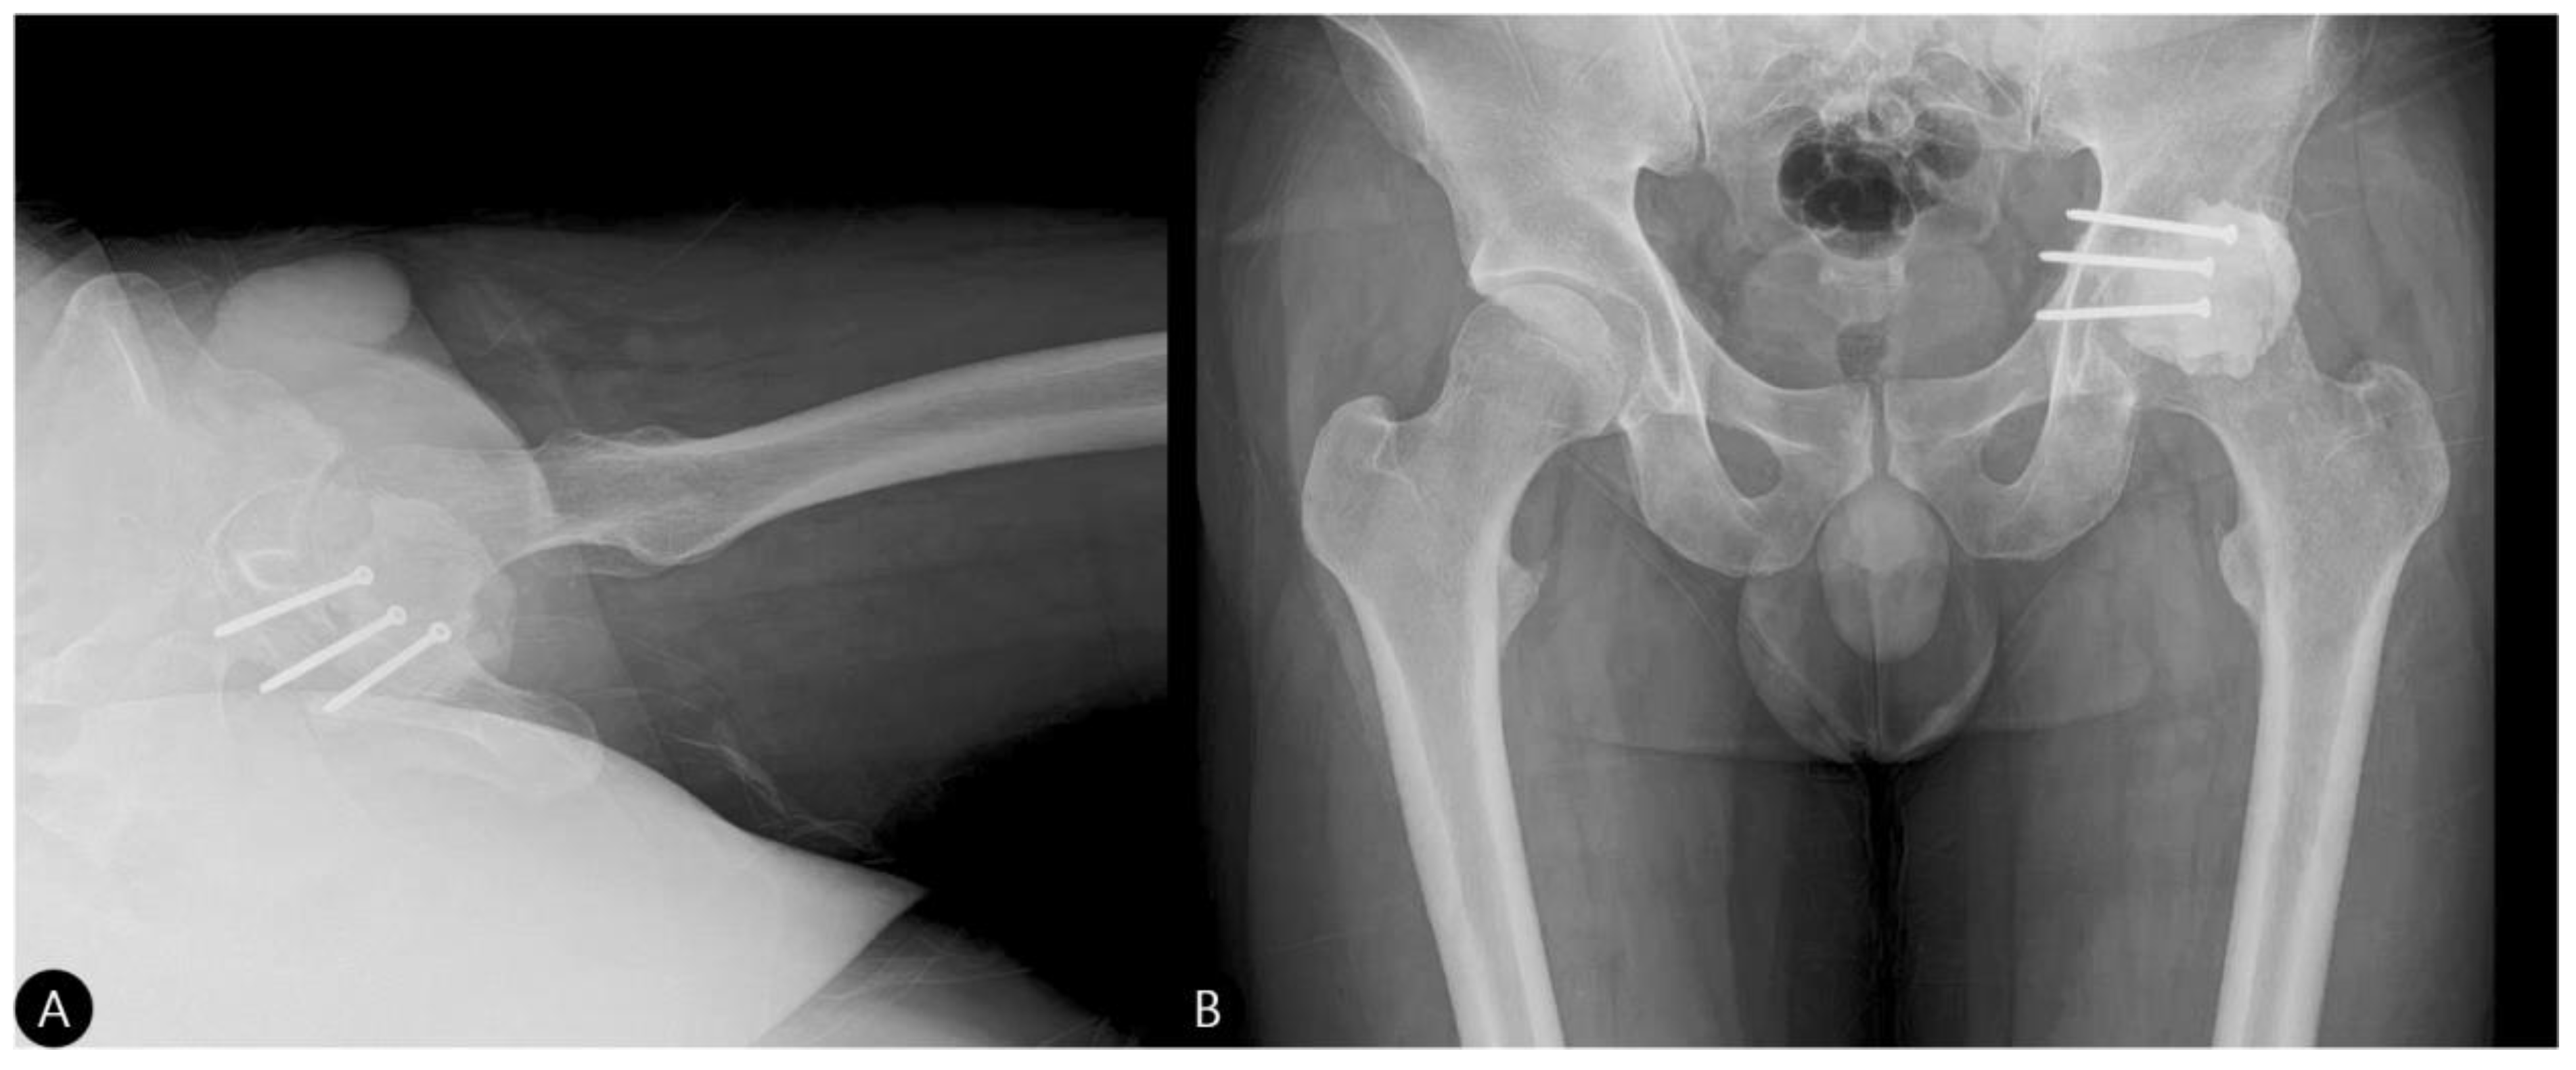

- 3 Months: Radiographs showed a stable hip construct with no signs of subluxation or screw migration (Figure 7). The patient had returned to activities of daily living without major discomfort. The mHHS was 78/100.